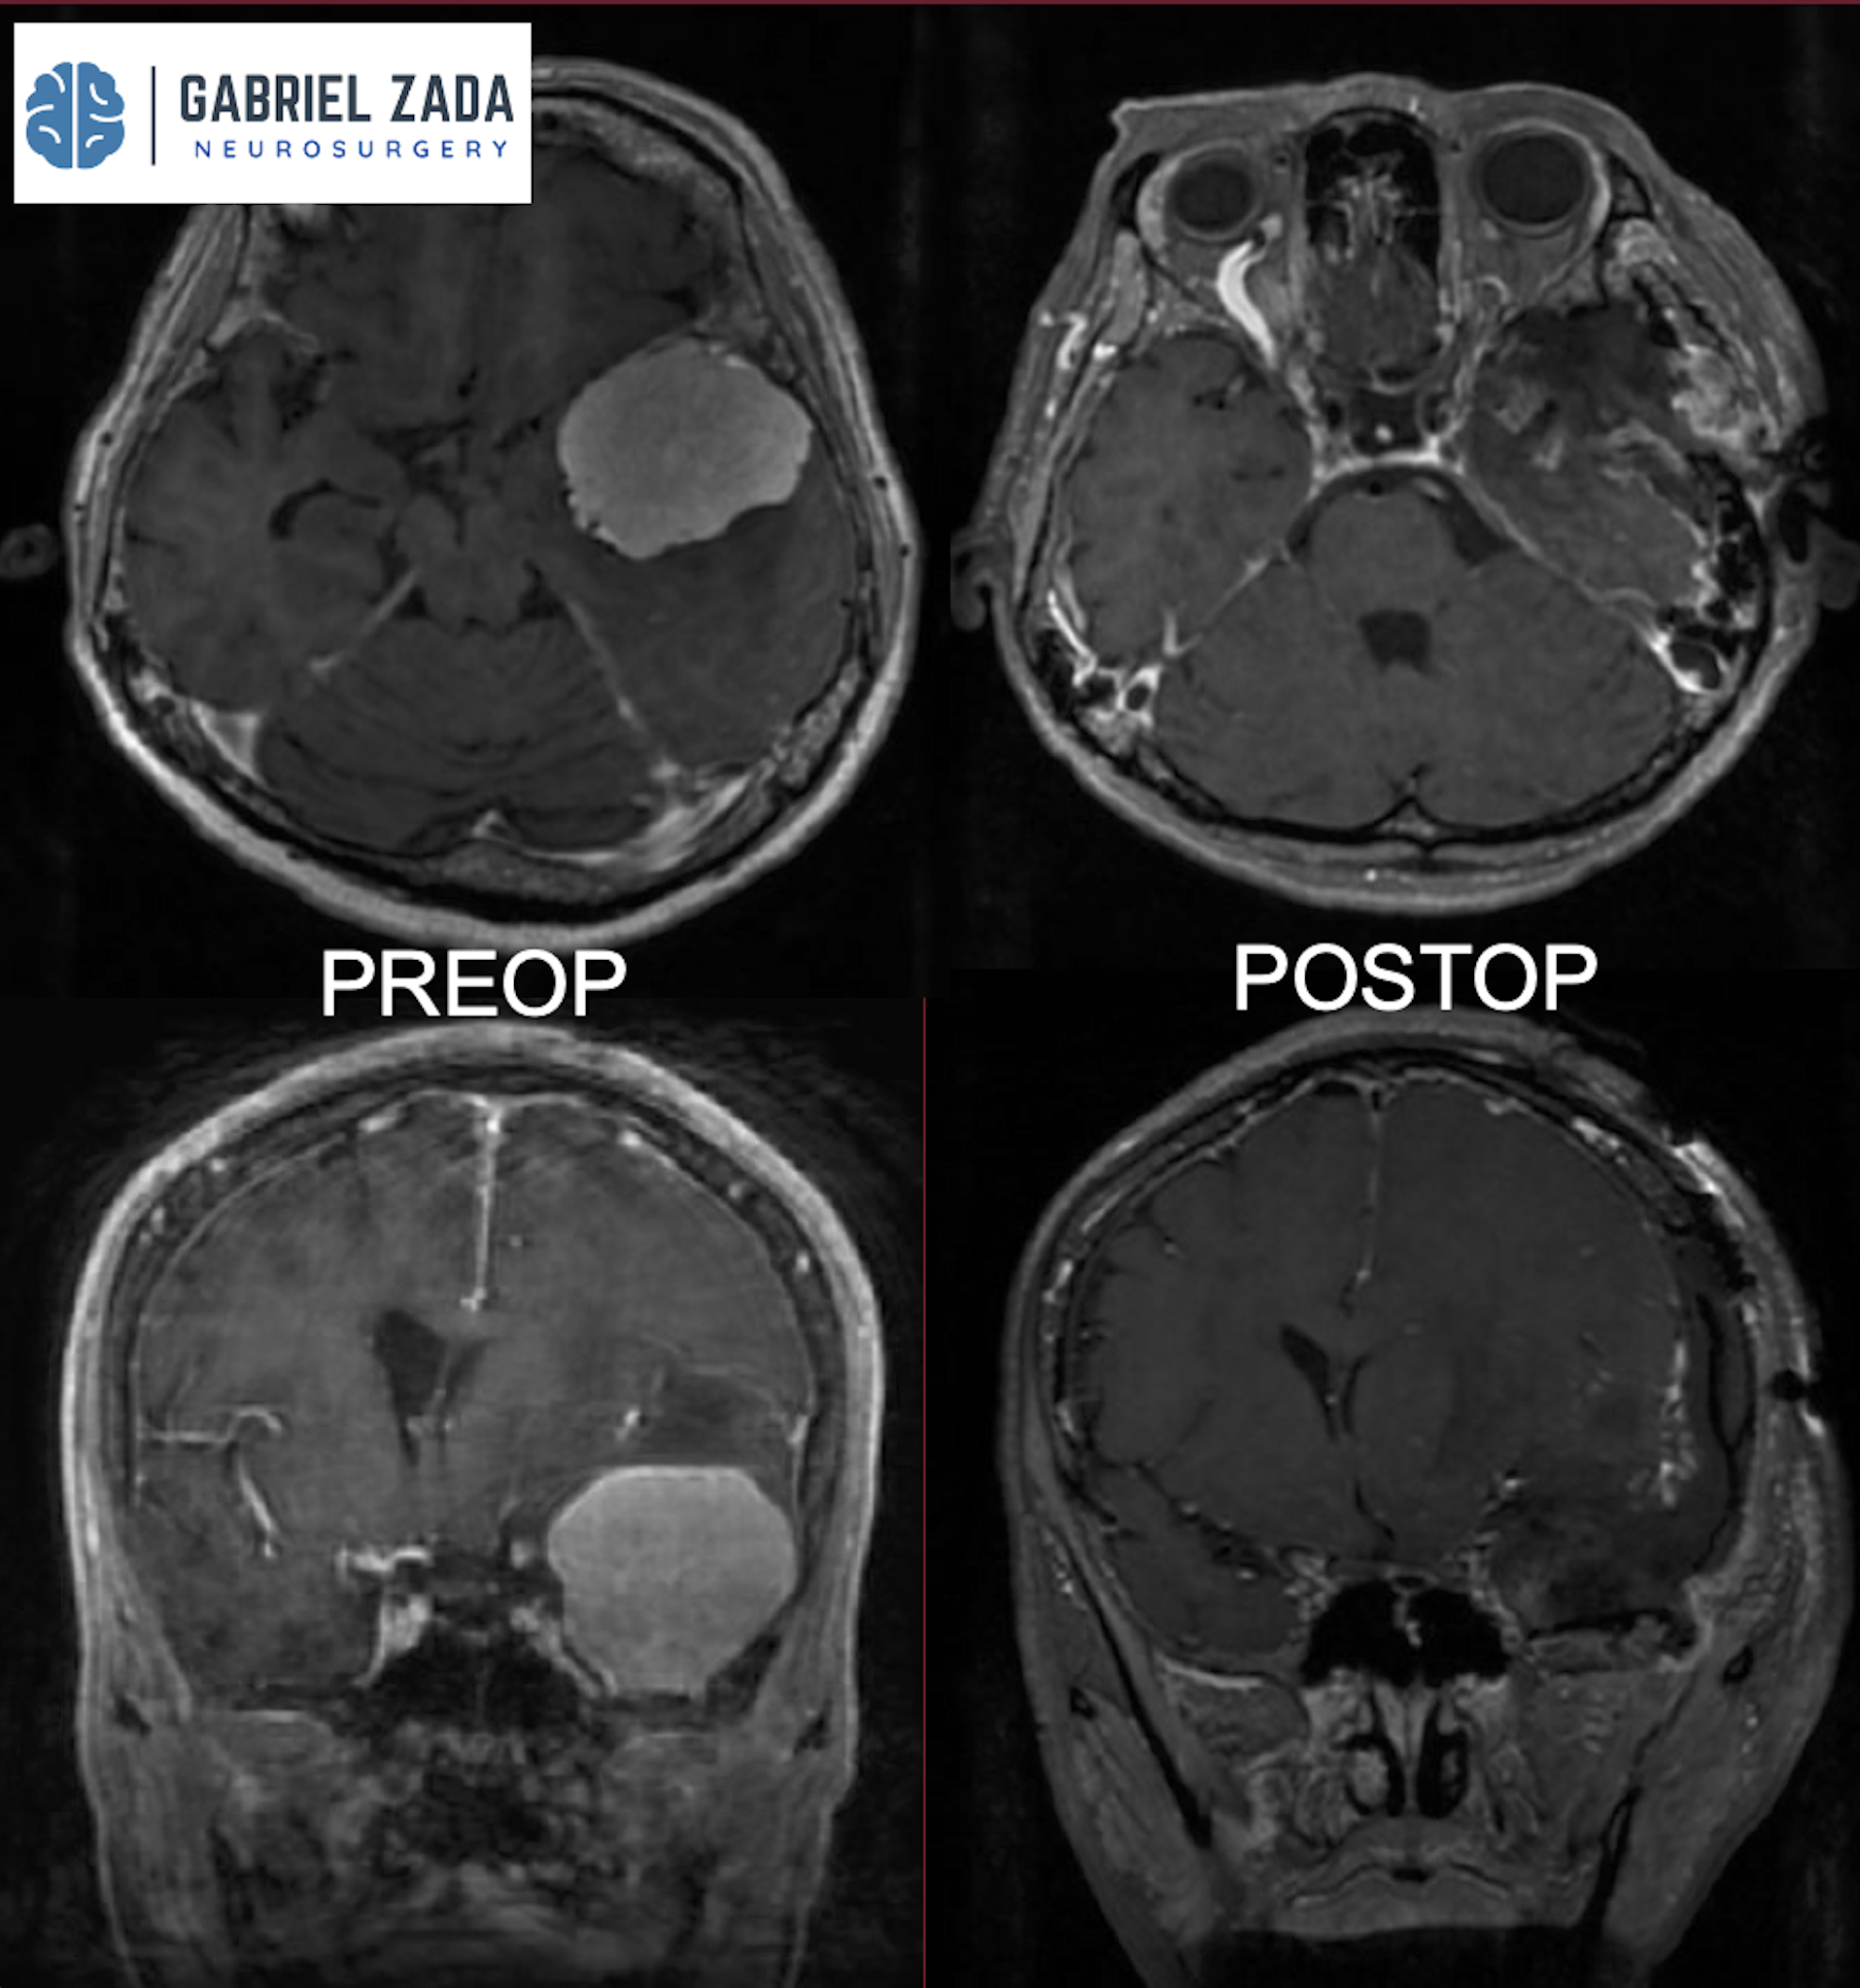

Explore this comprehensive gallery featuring pre‑ and post‑operative imaging of patients with skull‑base tumors treated by Gabriel Zada, MD, MS, FAANS, FACS. These cases highlight Dr. Zada’s expertise in advanced neurosurgical techniques and outcomes.

*Representative cases shown for educational purposes. All images de-identified. Individual results vary.